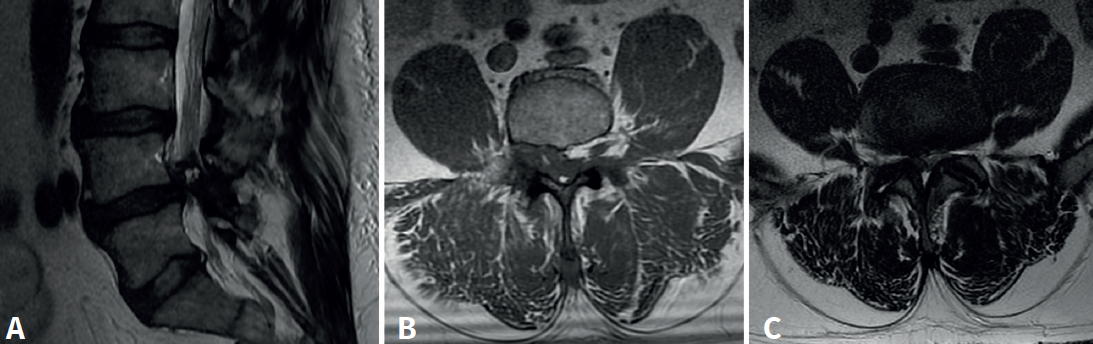

Cincuenta días tras el accidente se realizó fusión lumbar instrumentada L4-L5 con inserción de dispositivo intersomático por vía transforaminal derecha. En el segundo día postoperatorio presentó empeoramiento del dolor, objetivándose en la tomografía computarizada (Figura 2) malposición del tornillo L5 izquierdo que invadía el canal. Se reintervino a los 5 días corrigiendo el trayecto del tornillo. Sin embargo, persistió el dolor. La revaluación del caso, sumada a los hallazgos de EMG, motivó estudios complementarios de pierna y trayecto ciático (Figuras 3 y 4), detectándose una masa tumoral en el fémur izquierdo compatible con sarcoma fusocelular.

Figura 2. Tomografía computarizada lumbar postoperatoria en corte axial. Tornillo pedicular izquierdo de L5 mal posicionado, con violación de la pared medial del pedículo e invasión parcial del canal vertebral.